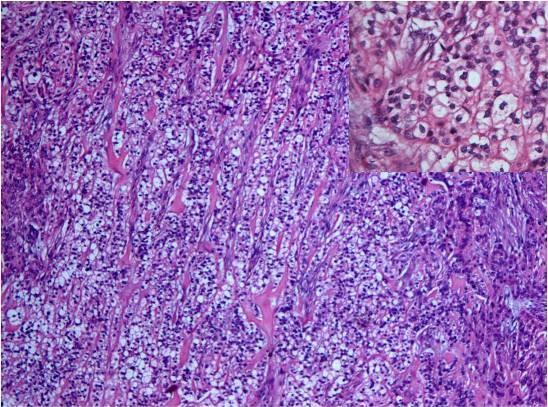

A 47-year-old Asian Caucasian woman presented with a painless swelling at the right lateral border of the tongue with an intact overlying mucosa. There were no other associated complaints. The lesion was excised and subjected to histopathological examination that revealed an interesting and unusual morphology of polymorphous low-grade adenocarcinoma.

一名47岁的亚裔白种女性,舌右侧缘出现无痛性肿胀,表面黏膜完整。无其他相关主诉。病变切除后进行组织病理学检查,显示出多形性低度恶性腺癌有趣且不寻常的形态。